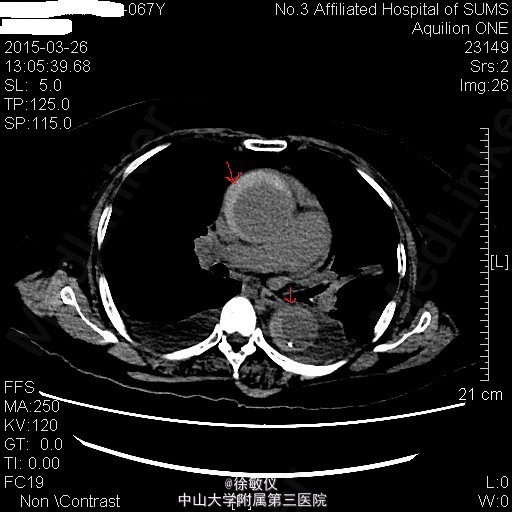

于急诊输液、止呕治疗后呕吐停止,胸闷持续3小时后症状减轻,予阿司匹林、氯吡格雷、立普妥负荷量口服后收入我科。 入院后查胸部、腹部ct发现有主动脉夹层。 诊断:冠状动脉粥样硬化性心脏病;主动脉夹层。

讨论:典型的急性主动脉夹层病人往往表现为突发的、剧烈的、胸背部、撕裂样疼痛。严重的可以出现心衰、晕厥、甚至突然死亡。该患者仅表现为胸闷,症状不典型。